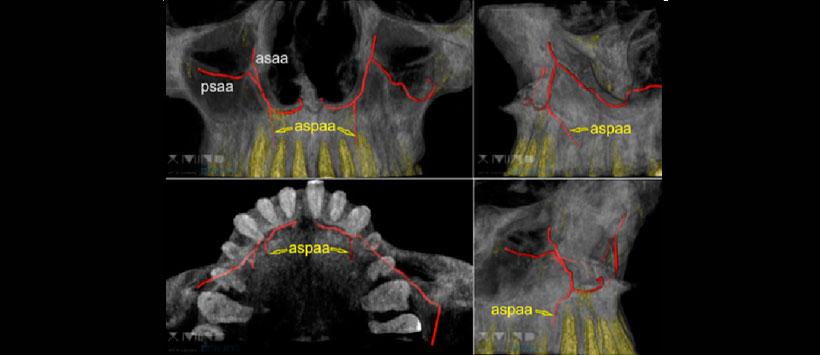

Figura 4: Rastreo automático de la arteria alveolar palatina anterior superior recién descubierta (aspaa; «Arteria Kurrekii») en las exploraciones XMIND-TRIUM-CBCT de rutina con tamaño de vóxel 75 μm.

Figura 5: La distribución estadística de la ubicación de salida palatal del aspaa recientemente encontrado «Arteria Kurrekii» se correlacionó con las proyecciones anatómicas de la posición del diente, tanto para la investigación de la cabeza del cadáver humano como de las detecciones en XMIND-TRIUM-CBCT-scans. El análisis histológico de los contenidos de aspaa muestra un vaso sanguíneo con la estructura típica de una arteria con forma redonda y capa muscular-celular gruesa.